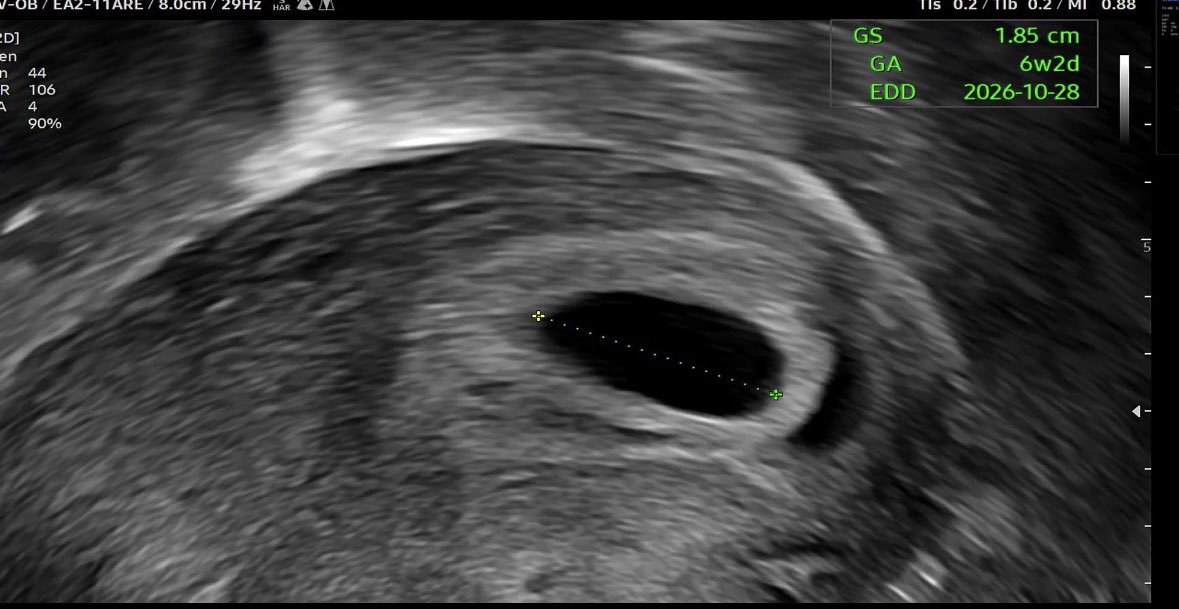

제가 임신을 했어요🥹 기다렸던 임신이라 반가우면서도 앞으로 메이크업은 어렵겠다 생각하니 아쉽기도 해요 사실 몰랐는데 잠이 이상할정도로 쏟아지고 살짝 입덧이 오면서 알게되었어요 벌써 입덧지옥이 시작되었구... 아쉽지만 지난달 오더분을 끝으로 메이크업 오더는 잠정 중단될 것 같습니다🥲

이불 _ bjd face up tweet media

축하해주신 모든 분들께 너무너무 감사드려요🥹🤍 배땡김, 입덧이랑 졸림이 이상할 정도로 너무 심해서 병원 다시 다녀왔더니 쌍둥이라고 하더라구요 자연임신이라 생각도 못했는데 어쩐지 증상들이 더블이벤트 중이었나봐요😭 많은 분들께서 축하해주셔서 따로 글남겨둡니다🫶 진심으로 감사합니다!